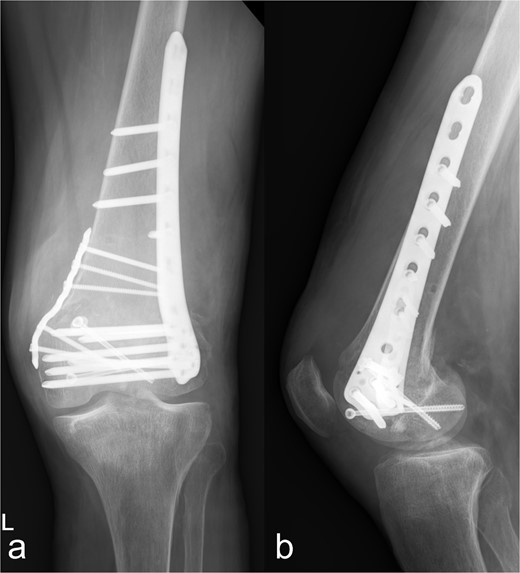

Osteosynthetic treatment via an open approach to the knee joint presented the multifragmentary femoral fracture radiating into the joint with an osseous avulsion of the lateral collateral ligament and posterolateral insertion of the anterior cruciate ligament (Fig. 1b). After reduction of the fracture fragments with temporary fixation using K-wires, an LCP 6-hole plate (Synthes®) was positioned medially and a 7-hole LISS plate (Synthes®) laterally and anchored with multiple screws (Fig. 2a and b). The osseous avulsion of the anterior cruciate ligament was fixed with a 3.5-mm SharkScrew®, the avulsion of the lateral collateral ligament with two FibreWire Loops®.

Treatment patterns of supra-intracondylar multifragment fracture (33C3.2). (a) The anterior-posterior and (b) lateral radiographs show a correct position of the osteosynthesis material with an nearly anatomical fracture position.

In the fractures described, the osteopenic bone texture with rarefied spongiosa, thinning of the cortical bone and dislocated fragments present an intraoperative challenge in achieving a good reduction in an axially correct position and hardware fixation. In order to achieve the best possible primary stability in the acute situation and to minimize the occurrence of secondary fractures, locking plates, screws with different threads, intramedullary nails, wire cerclage, total endoprostheses, and additional PMMA cement augmentation are used [9–14]. In our patient, this was achieved by means of plate osteosynthesis and additional screws. In the complex multifragment fracture of the distal os femoris, lateral and medial plate insertion was performed to achieve sufficient stability (Fig. 2a and b). This minimizes the development of pseudarthrosis, while lateral and medial plate osteosynthesis does not have a negative influence on vascularity [15, 16]. However, even in nonorgan transplanted patients after optimal osteosynthesis of a distal femur fracture, a second surgery is necessary in every eighth patient [17]. In the case of multiple localizations with more complex fracture courses, several operations and follow-up procedures may be necessary. This necessitates extensive postoperative care, especially in organ transplant patients. Chiou et al. [18] report a 62.5 % mortality rate over the course of 1076 days in lung transplant patients after treatment of a fracture of the lower extremity.